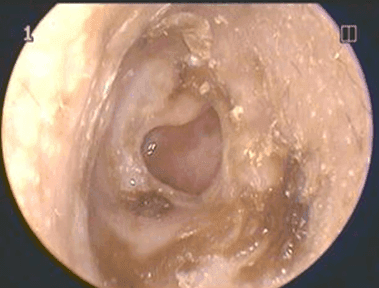

Kulak hastalıklarının neden olduğu kulak ağrıları da genellikle iki temel hastalığa; dış kulak hastalıklarına ve orta kulak hastalıklarına bağlıdır. Dış kulak hastalıkları sonucu gelişen ağrılar genellikle dış kulak yolu iltihaplanmasına bağlı olur.

En önemli nedeni kulak karıştırmak olan dış kulak yolu iltihapları özellikle kulak kepçesini çekmek, hareket ettirmekle artan sızı vasfındadır ve sıklıkla dış kulak yolu dediğimiz kulak kepçesinin ortasından derine doğru uzanan kanalın şişmesi ve tıkanması ile birlikte görülür.

Bu tahrişin üzerine binen mikroplar kötü kokulu irin vasfında bir akıntıya ve dış kulak yolu ve kulak kepçesinde şişlik, kızarıklık, hareket ile artan ağrı ile karakterli mikrobik iltihaba da neden olabilirler. Daha nadiren de olsa uçuk, zona gibi iltihaplanmalar ve tümörler de dış kulak yolunu tutarak ağrıya neden olabilir.

Orta kulak iltihabı ise büyük çoğunlukla çocukları İlgilendiren bir hastalıktır. Genellikle nezle, grip gibi üst solunum yolu hastalığı esnasında veya hemen sonrasında ateş, halsizlik, kırıklık, iştahsızlık, karın ağrısı, ishal gibi belirtiler ile birlikte kulak ağrısı, sıklıkla işitme kaybı, dolgunluk hissi ve bazen irinli kulak akıntısı ile birlikte görülür.